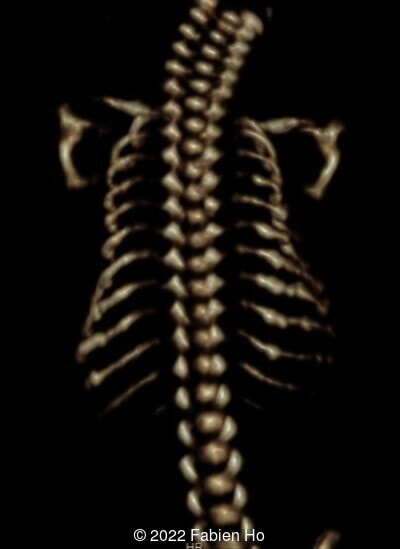

A CT scan was subsequently performed at 32 weeks gestation

The prenatal CT scan showed:

- Low bone density of skull and lower limbs

- Moderately narrowed and bell-shaped thorax

- Numerous bone calluses of the posterior arcs of the ribs

- Normal bone density of the spine

- No platyspondyly

- Normal pelvis without iliac spine or other anomaly

- Very short long bones with curved femurs, tibias and fibulas. The curvature of the long bones reaches a 90° angle concerning for fracture. Upper limbs are moderately curved without fracture.